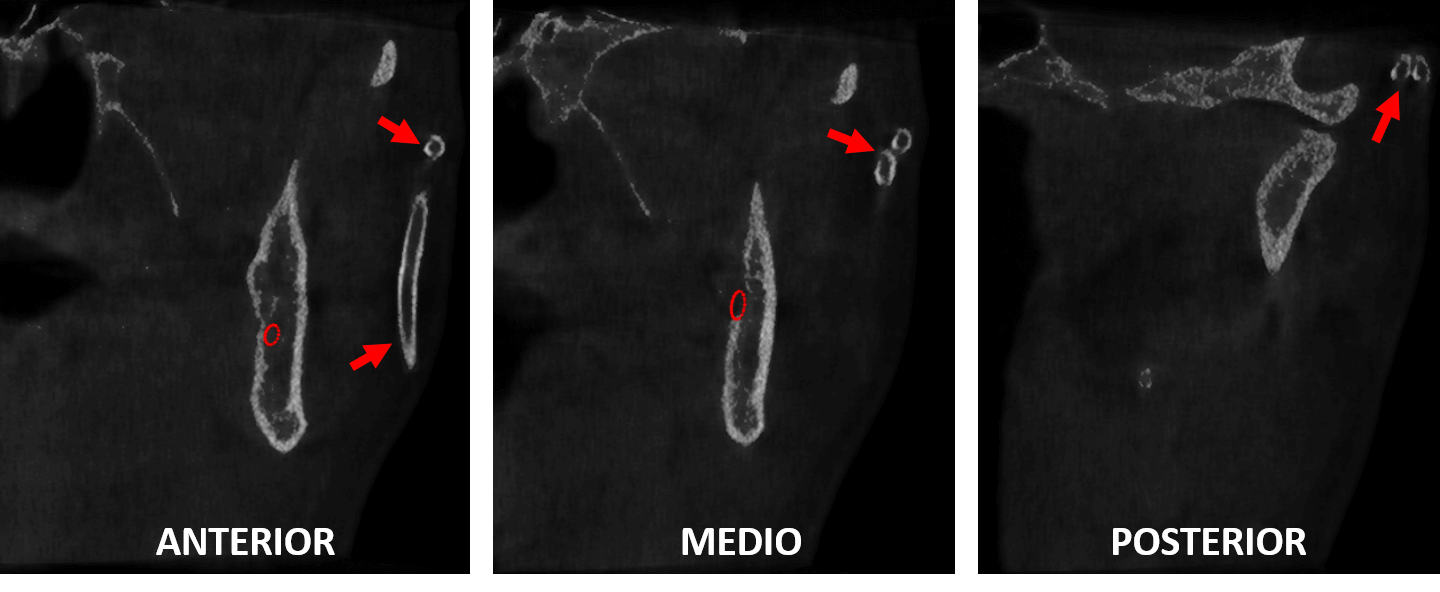

Fig.3

En cortes laterales (Fig.3) se observa el trayecto del dispositivo tubular (flechas rojas) en el lado izquierdo, a nivel del tejido blando facial.